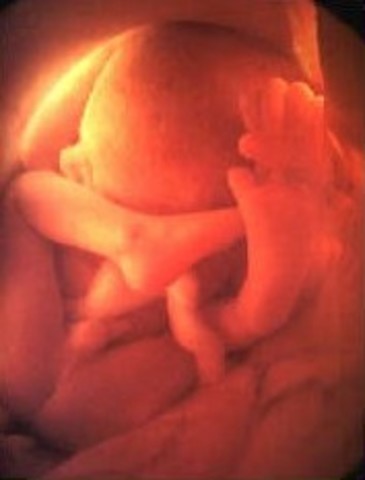

• week 27

week 27

Looks are almost fully developed. Retina at the back of baby's eyes are starting to develop.